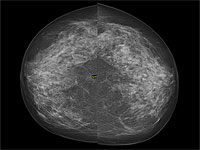

Донор спермы с генной мутацией, радикально повышающей риск развития рака, стал отцом 200 детей по всей Европе. Это выяснилось в ходе масштабного расследования, проведенного крупными вещателями, включая CBS News, BBC News.